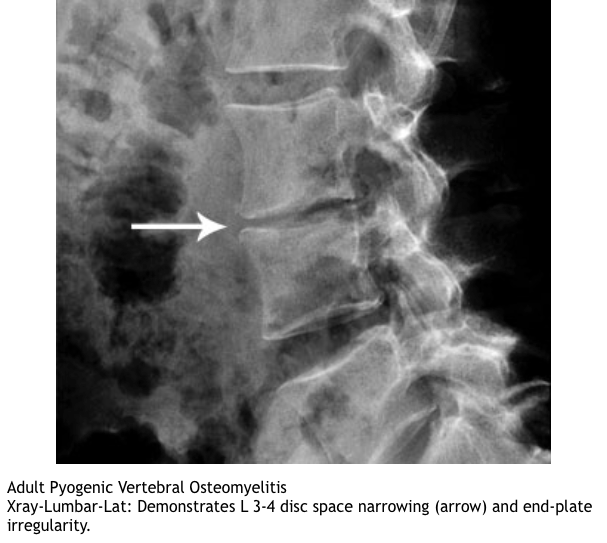

xrays